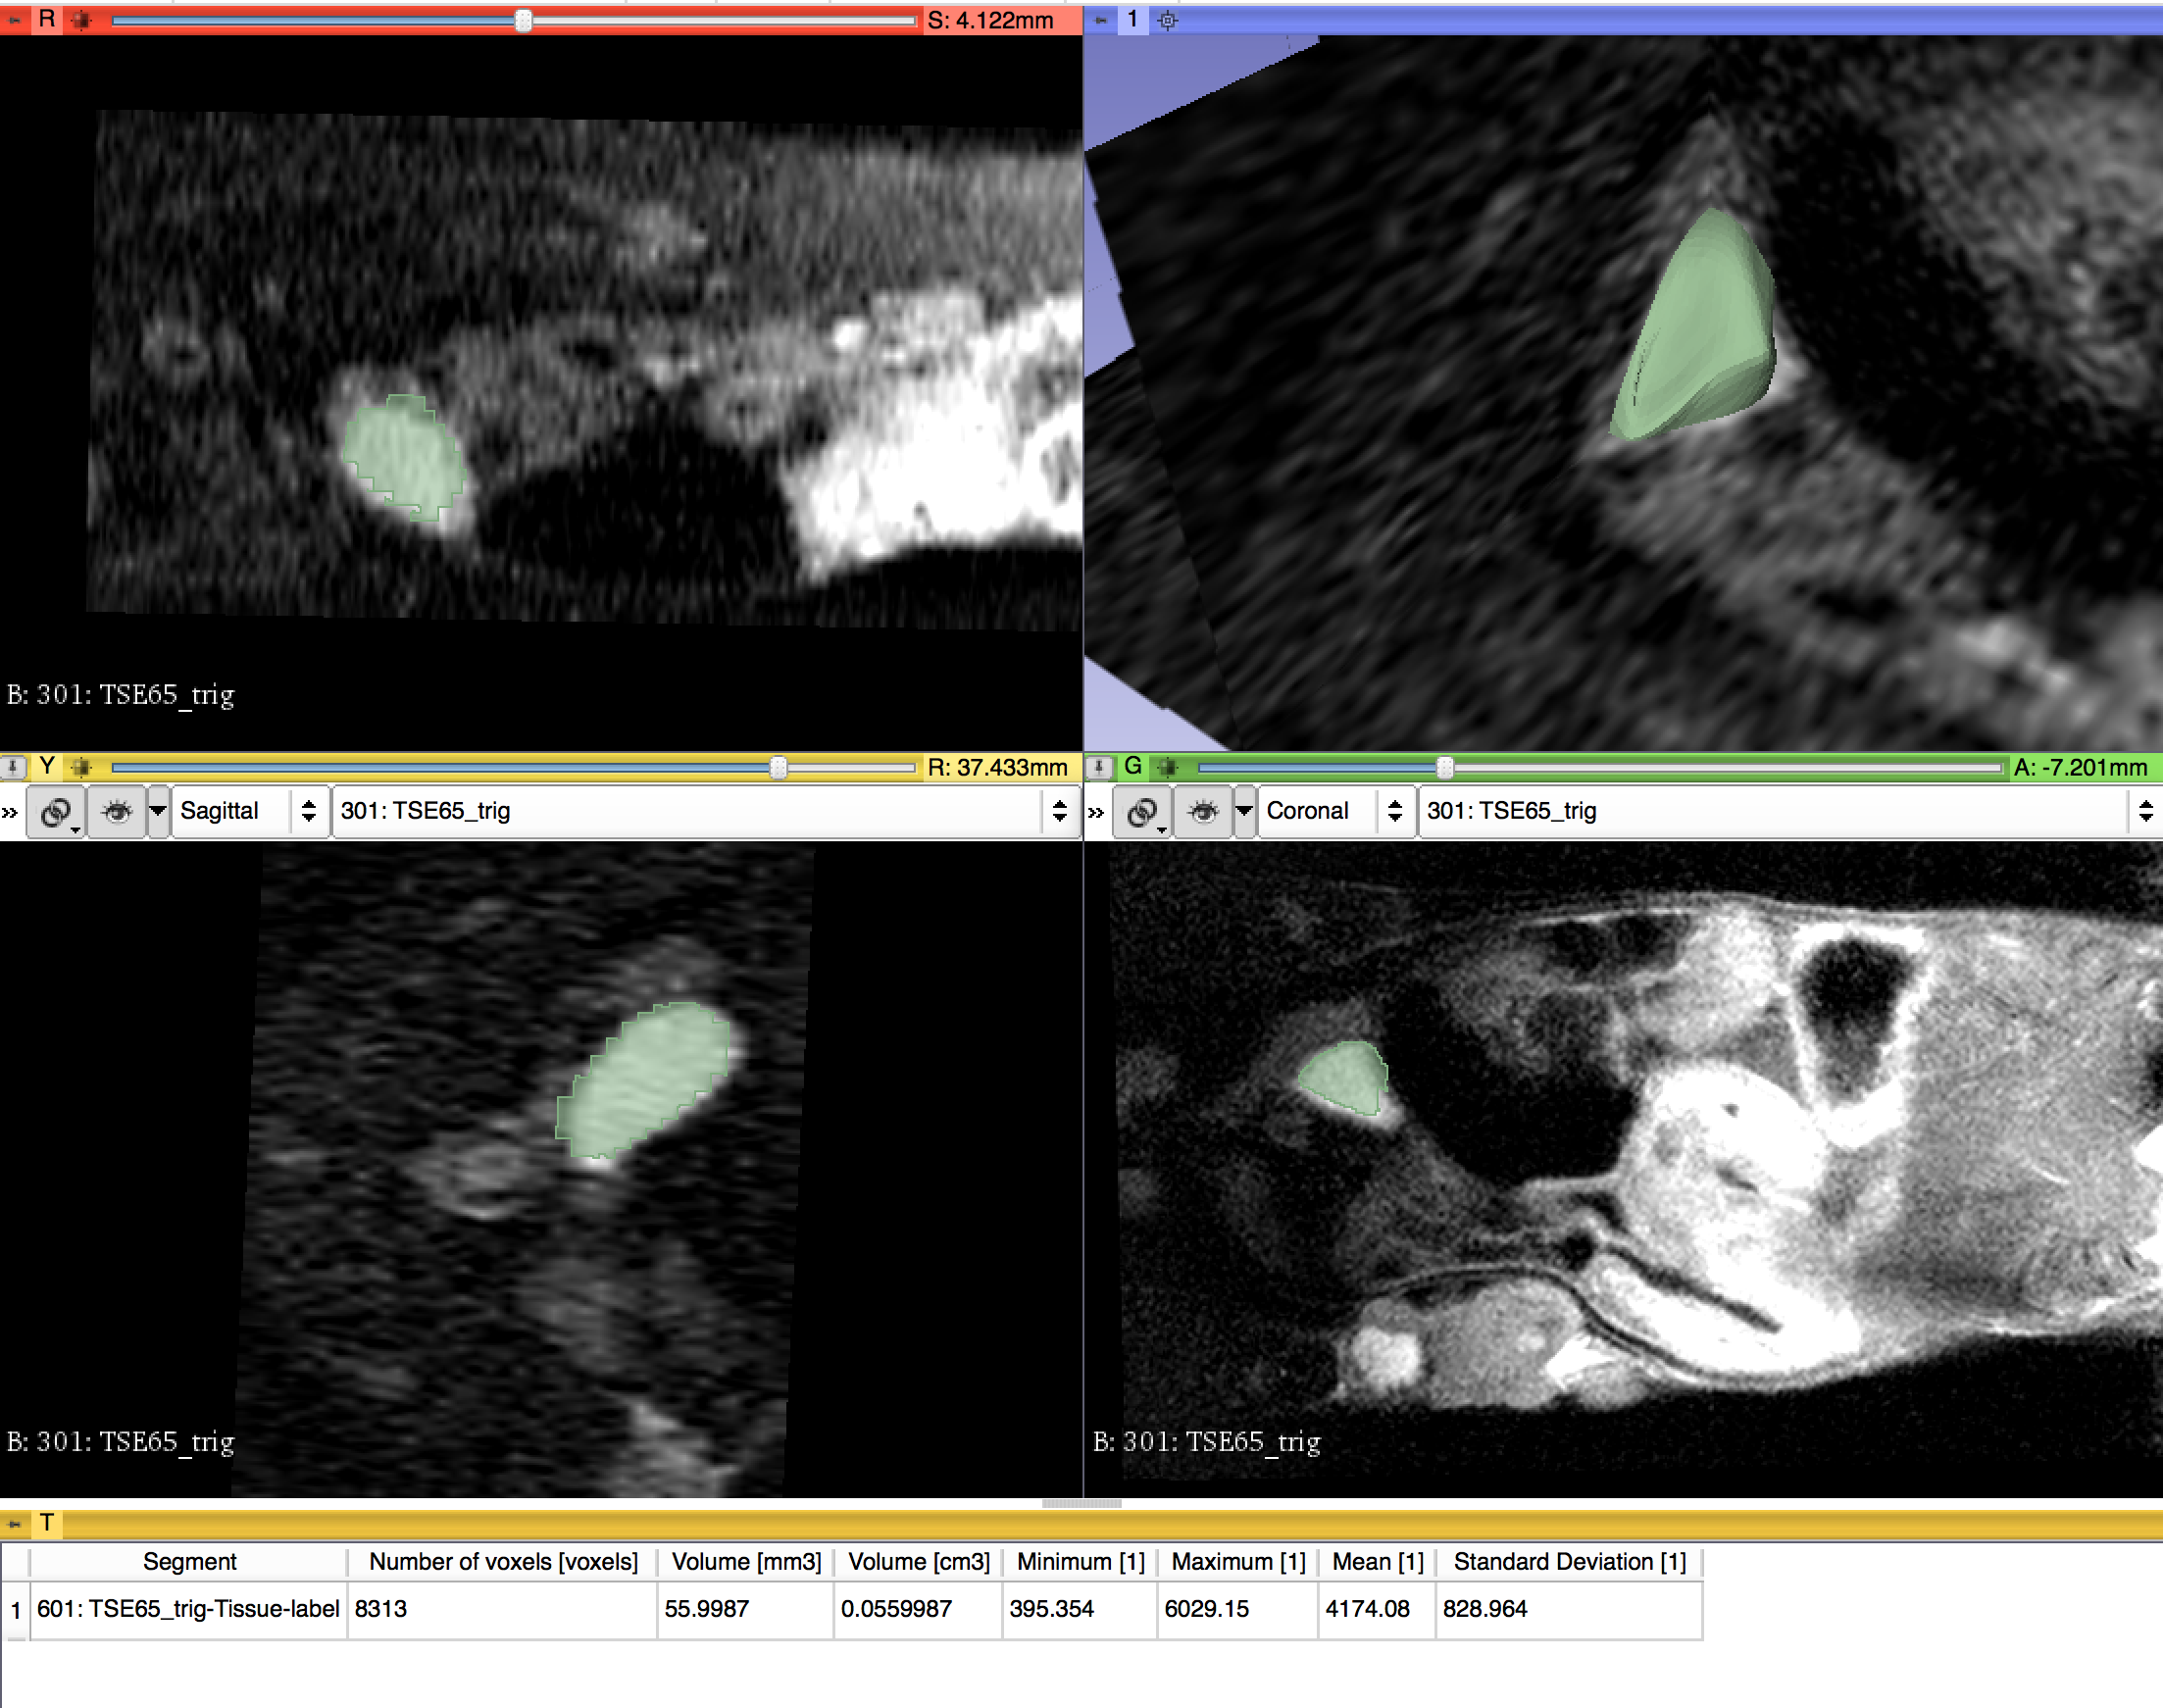

Small Animal Quantitative Imaging

For this project, we aim to bring small animal MR datasets in DICOM format and repeat the process developed for the QIICR program to segment a lesion (a Neuroendocrine Tumor in this case), convert the segmentation to a DICOM segmentation using the DCMQI slicer extension, and finally measure the segmentation using the Quantitative Reporting module. Our aim is to develop a set of repeatable analysis steps we can put into place to analyze additional datasets in our lab.

- Develop a set of processing steps for lesion analysis that are repeatable for other small animal datasets. Access if clinical tools from the QIICR program will apply to small animal MR datasets as well.

- Test DCMQI tools on a Small Animal MR dataset. Access if small animal DICOM headers are similar enough to clinical scanners.

- Use Slicer segmentation tools to generate a label map of the lesion.

- Segment lesion using Slicer Segmentation Wizard

- Reprocessed successfully and measured DICOM segmentation object using Quantitative Reporting module